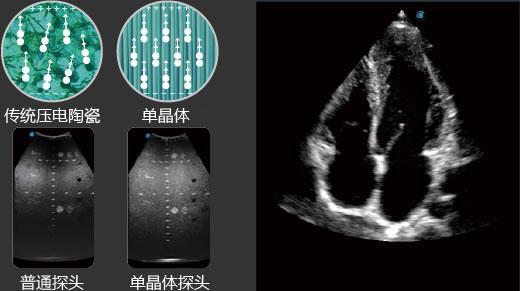

先进的单晶体探头具备优异的声学性能和超高的频带宽度,以更高的穿透力 和优异的图像性能为成像困难的患者提供更多的诊断信息。